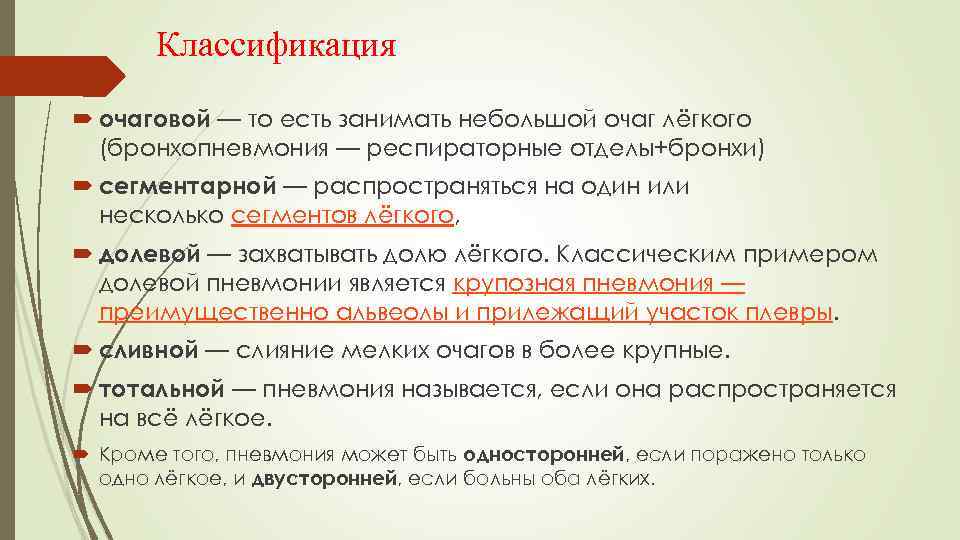

Классификация очаговой — то есть занимать небольшой очаг лёгкого (бронхопневмония — респираторные отделы+бронхи) сегментарной — распространяться на один или несколько сегментов лёгкого, долевой — захватывать долю лёгкого. Классическим примером долевой пневмонии является крупозная пневмония — преимущественно альвеолы и прилежащий участок плевры. сливной — слияние мелких очагов в более крупные. тотальной — пневмония называется, если она распространяется на всё лёгкое. Кроме того, пневмония может быть односторонней, если поражено только одно лёгкое, и двусторонней, если больны оба лёгких.

Классификация очаговой — то есть занимать небольшой очаг лёгкого (бронхопневмония — респираторные отделы+бронхи) сегментарной — распространяться на один или несколько сегментов лёгкого, долевой — захватывать долю лёгкого. Классическим примером долевой пневмонии является крупозная пневмония — преимущественно альвеолы и прилежащий участок плевры. сливной — слияние мелких очагов в более крупные. тотальной — пневмония называется, если она распространяется на всё лёгкое. Кроме того, пневмония может быть односторонней, если поражено только одно лёгкое, и двусторонней, если больны оба лёгких.